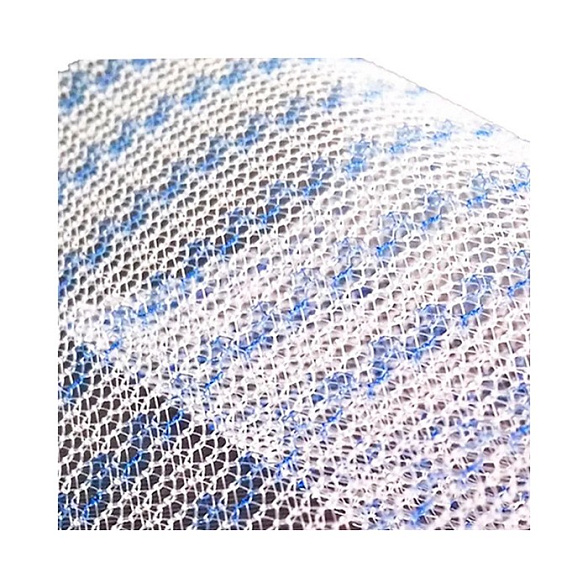

Эндопротез-сетка (сетка хирургическая) полипропиленовый для восстановительной хирургии ЭСФИЛ лёгкий, 30х10 см, Линтекс

Эндопротез-сетка полипропиленовая ЭСФИЛ лёгкий для восстановительной хирургии

Эндопротез-сетка ЭСФИЛ лёгкий от компании «Линтекс» — это современный полипропиленовый имплантат, разработанный для эффективного и надежного восстановления анатомических структур в хирургической практике. Изделие размером 30х10 см представляет собой легкую макропористую сетку, которая служит прочным каркасом для укрепления тканей и стимулирования их естественной регенерации.

- Минимальная реакция тканей: Макропористая структура и легкий вес материала способствуют быстрому прорастанию соединительной ткани, формируя прочный рубцово-сетчатый комплекс с минимальным риском образования грубых спаек.

- Удобство в работе: Материал легко моделируется и кроится непосредственно в операционной, идеально адаптируясь к анатомическим особенностям пациента. Сетка не скручивается и хорошо держит заданную форму.

| Тип структуры | Макропористая, легкая, не расслаивающаяся |